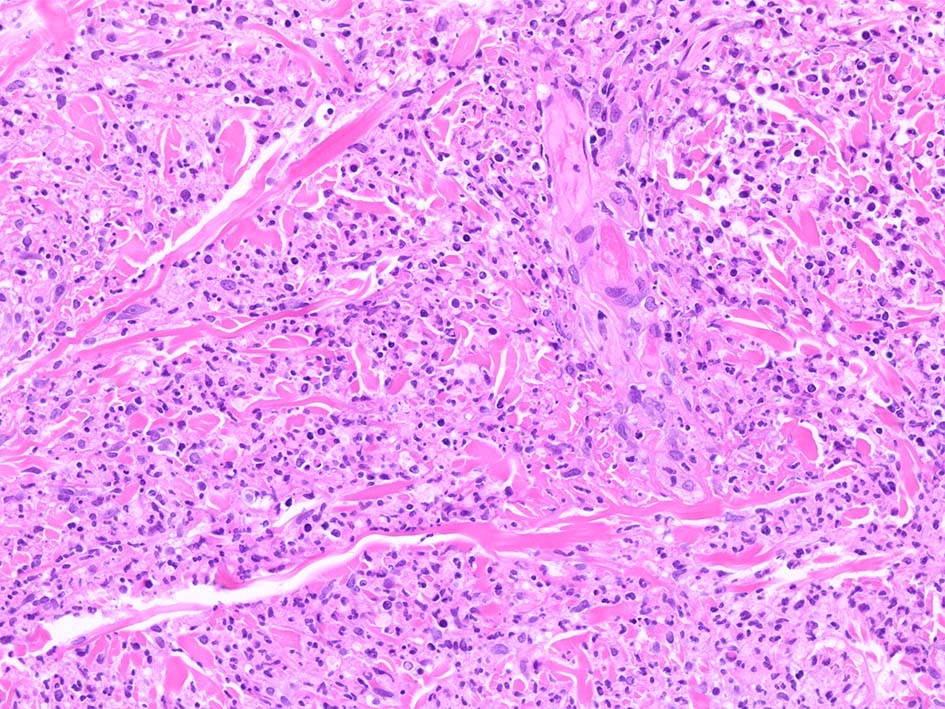

HE x40. 表皮下水疱あり. 真皮上層は浮腫状. 真皮から皮下組織にかけて, 多数の好中球が浸潤している. リンパ球, 好酸球が混在, 核破砕物を貪食するマクロファージが増加. 膠原線維にはところどころ変性が見られる.

真皮上層には核破砕物が多く, 好中球浸潤が認められる. 慢性炎症性細胞も浸潤している.

フィブリノイド壊死を呈する血管炎は認められない.

皮下脂肪織炎病変には局所的なhemophagocytosisが認められる. 血管にはfibrinoid necrosisは見られない。